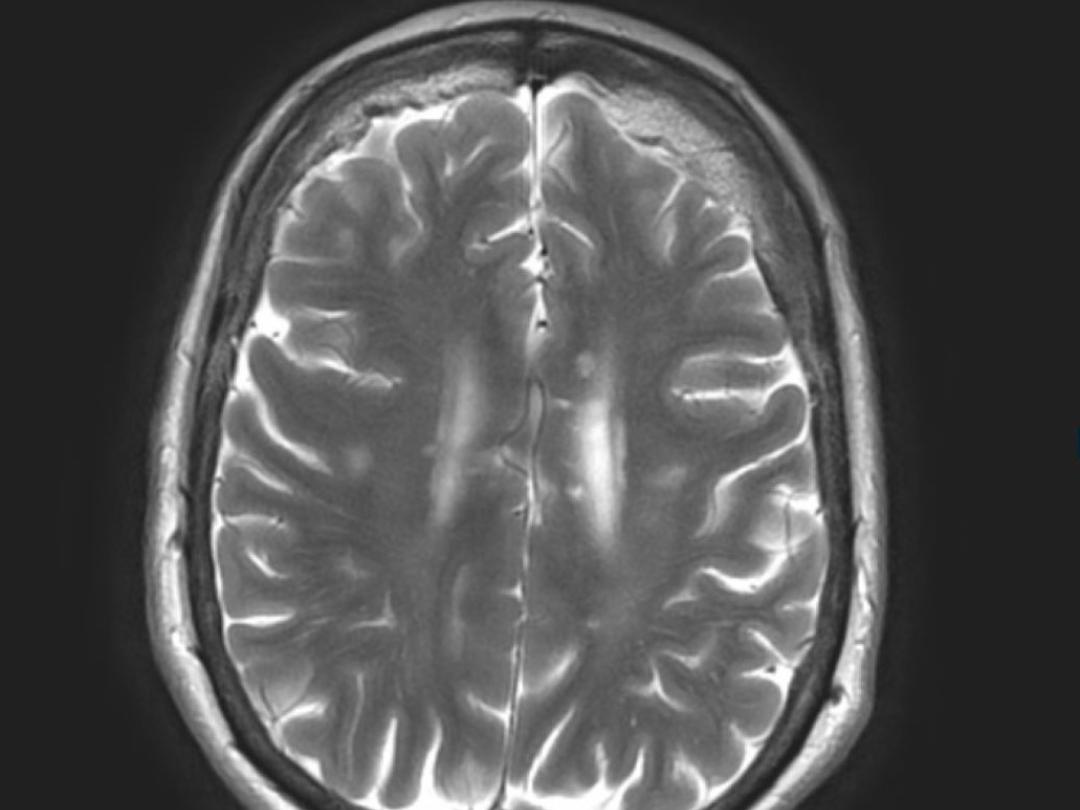

In dit artikel presenteren wij een 71-jarige vrouw met meerdere episodes van afzonderlijke klachten zoals een afasie, gedragsverandering, geheugenverlies en draaiduizeligheid met tinnitus. MRI van de hersenen liet kenmerkende signaalveranderingen van het corpus callosum zien, waardoor werd gedacht aan het syndroom van Susac. Met een afwijkend FAG en audiografie was de trias compleet. Hierop kreeg de patiënte een behandeling met immunosuppressiva, waarna cognitieve verbetering optrad.